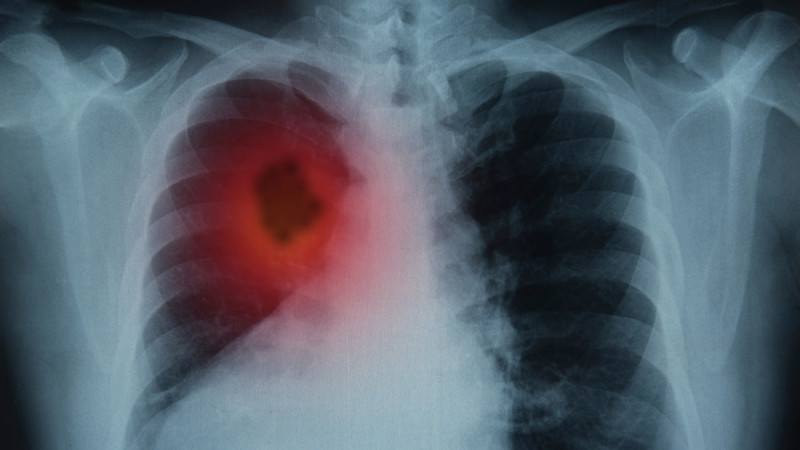

Врач назвал эффективный способ выявления рака легкого

Рак легкого является одним из наиболее агрессивных онкологических заболеваний, но для его диагностики существует действенный метод - НДКТ-скрининг, способный спасти миллионы жизней. Об этом в интервью "Ленте.ру" рассказал заслуженный врач, профессор Петр Яблонский, передает TengriHealth.

Специалист пояснил, что сложность выявления онкологических заболеваний легких обусловлена отсутствием нервных окончаний в нижних отделах дыхательной системы. Поэтому заболевание может долгое время протекать бессимптомно, а отдельные проявления - кашель или усталость - ничего не подозревающие больные часто списывают на простуду или возрастные изменения.

"Без лечения медиана выживаемости у больных даже на первой стадии составляет всего около 16 месяцев. А у нас, согласно официальным данным, 43 процента новых случаев выявляется уже на четвертой стадии", - заявил главный торакальный хирург Минздрава России.

В этой связи, отмечает профессор, врачебное сообщество выступает за внедрение скрининга с помощью низкодозной компьютерной томографии (КТ). Если диагностировать рак легкого на первой стадии, пятилетняя выживаемость пациентов составляет от 92 до 98 процентов, указывает врач.